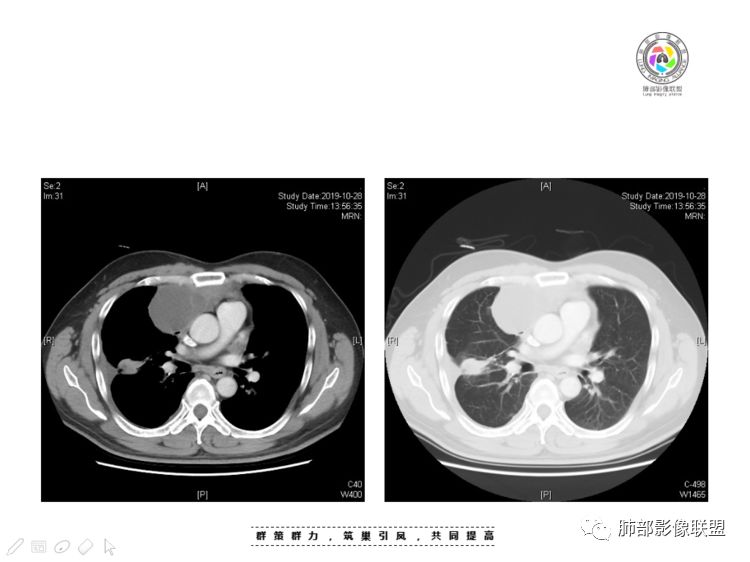

穿越七海的风:右前纵隔占位,恶性肿瘤,生殖来源?右肺实变是占位or肺不张?考虑为部分肺不张FeNo:右前纵隔占位,右肺结节,胸膜凹陷,小尾巴,右肺不张,考虑恶性杨旭华:恶性,前纵隔肿物,与血管关系密切,上腔静脉变窄,右肺野一元论考虑叶间裂增厚,恶性胸膜间皮瘤可能大小丽:到底是纵隔来源还是胸膜来源?我怎么倾向于胸膜来源,和叶间胸膜关系密切,而且纵隔内上腔静脉是向内侧推移。胸膜肿瘤(间皮瘤?SFT?)包裹性胸腔积液?马春平(张家港市一院胸外科):前纵隔占位,左无名受压,右大量胸腔积液可能是胸导管汇入处侵犯受压,考虑纵隔鳞癌孙冰伟:右上纵隔占位,也感觉和叶间胸膜关系密切,右侧胸膜局限性增厚,考虑恶性可能性大灵:前纵隔占位,血性胸水,胸膜凹凸不平,查见肿瘤细胞,结合免疫组化考虑胸腺癌。鉴别胸膜间皮瘤。采莲:右前上纵膈旁可见类圆形肿块,纵隔血管内移,感觉来源于胸膜,肿块内密度低,似水样密度,右侧胸膜广泛增厚,少量胸腔积液。心包少量积液。考虑胸膜间皮瘤,鉴别肺癌并胸膜转移?水晶石头:患者中年男性,胸闷15天。有“高血压、慢性肾小球肾炎”病史。查肿瘤标志物正常,胸水提示渗出液,胸水病理查见瘤细胞。胸部CT:右肺上叶后段结节、斑片影,见胸膜牵拉、包裹积液及部分纤维条索灶,似见卫星灶,右侧胸膜增厚。前纵隔脂肪密度增厚,右侧可见类圆形低密度(液体)肿块,边缘光滑。综合考虑右肺腺癌并胸膜转移,结核可能。周太狼:考虑纵隔胸膜来源肿瘤,恶性,胸膜间皮瘤伴转移?徐飞:中年男性,影像为右侧胸腔及叶间积液,叶间胸膜增厚轻度强化。前纵隔右侧心缘旁团块,可见坏死。胸水见癌细胞,综合考虑恶性,胸腺癌伴转移。小赵:中年男性,血性胸水,常规查见癌细胞,李凡他实验阳性。胸部CT示前纵隔见不均匀密度影,与邻近大血管分界不清,囊变坏死明显,增强扫描呈不均匀强化,心包及右侧胸膜增厚,并心包及右侧胸腔少量积液。综合考虑胸腺癌。右肺中叶病变周围见多发纤维条索,支气管部分进入病灶,考虑炎性病变。流心明智:患者,男性,50岁。胸闷15天。高血压20年,慢性肾小球肾炎15年。肿标正常,胸水提示渗出液,胸水查见癌细胞。胸部CT:右肺肿块影,斑片影,索条影,可见胸膜牵拉、多发包裹积液,纵隔上腔静脉受累,心包受累。综合考虑:ROSE似腺?考虑右肺腺癌并胸膜转移,心包受累。鉴别胸腺Ca、淋巴瘤,纵隔病变不懂,等老师们精彩分析。王秀仙:前纵膈囊实性肿块,与纵膈分界不清,心脏大血管及上腔静脉受压向内后移,右侧后胸膜、侧胸膜增厚,右侧叶间裂不规则增厚,心包积液,根据腔静脉移位情况,考虑纵膈胸膜来源恶性肿瘤,胸膜间皮瘤?鉴别胸腺癌并胸膜转移。高广飞:上纵隔占位,右侧叶间胸腔积液,需考虑恶性自信人生:多发囊实性病灶,包裹性积液,考虑胸膜来源 只是没有看到壁结节,恶性胸膜间皮瘤巴伟:前上纵隔占位,胸膜及心包结节,考虑胸腺瘤或癌,右肺病灶,先考虑陈旧炎性病变。Lenle董:前纵隔占位,部分边缘模糊,病灶内囊变?坏死?上腔静脉受侵,考虑胸腺癌;叶间片状影,强化明显,炎性考虑。常志强:前纵隔囊实混杂密度肿块,边界不清,实性部分强化明显,结合胸水内见癌细胞,考虑恶性肿瘤伴转移。飞鹰行动:前纵隔占位,软组织密度及囊性密度,实性部分密度均匀,致密,病灶与周围血管分界不清,增强后病灶强化有类似不温不火强化,部分血管受侵犯,右肺见肿块样病变及条索状病变,一元论,考虑淋巴瘤,二元论,考虑胸腺瘤B2—B3伴右肺病变。尽量一元论考虑,淋巴瘤可能。看图说话:右肺索条病灶,边缘膨隆,胸膜牵拉,考虑右肺癌伴胸膜转移。晨:前纵隔囊实性肿块,与纵隔分界不清,右侧后胸膜、侧胸膜增厚,右侧叶间裂不规则增厚,考虑纵隔胸膜来源恶性肿瘤,考虑胸腺癌并胸膜转移。丽:中年男性,前纵隔囊实性肿块,呈偏心性生长,临近大血管受压推移,增强后实性部分不均匀强化,心包可见条形积液,考虑胸膜来源恶性肿瘤,胸腺癌可能大。另右肺多发斑片状高密度影及实变密度影,实变影呈均匀强化,右侧胸膜局限性增厚,考虑炎性病变。小飞:右前纵隔囊实性占位,实性部分明显强化,右侧叶间胸膜增厚,右侧胸腔积液,心包积液,考虑恶性胸腺瘤!尘缘:支持恶性胸腺瘤(囊实性肿块,实性强化,且侵犯纵隔,脂肪间隙模糊)伴肺内及胸膜转移。浪迹天涯:考虑侵袭性胸腺瘤——胸腺前纵隔占位,周围脂肪间隙模糊不清。尘缘:不除外另一种可能:二元,肺内腺癌合并胸膜转移,纵隔的畸胎瘤可能。一米阳光:晨读中年男性,右肺结节影,叶间裂及胸膜增厚牵拉,右侧胸水。心包多发结节改变。胸水查见癌细胞。考虑,腺癌并转移。鉴别,胸膜间皮瘤并转移前纵隔囊实性占位,二元考虑。心灵鸡汤:老年男性,右肺中叶外段长条状软组织密度影,边缘膨隆,邻近胸膜牵拉,部分胸膜有栽脏,右中叶外侧段支气管堵塞,常规考虑恶性肿瘤,腺癌可能,结核、鳞癌不除外,另右肺上叶斑片影,小叶性肺不张?右前纵隔囊实性不规则形密度影,其内见部分脂肪样极低密度影,与邻近血管边界不清,心包外膜有侵犯,增强未见纵隔窗平扫,实性及分隔见增化,其内低密度影未强化,考虑低度恶性纵隔肿瘤,间皮瘤可能,畸胎瘤、淋巴瘤待排,建议支气管镜及穿刺活检。曹志勇:右前纵隔考虑来源于胸膜的恶性肿瘤,右肺内病灶考虑鳞癌,二元德芙~云味:中年男性,右肺见结节、斑片影,右侧包裹积液、胸膜牵拉,纤维条索,前纵隔囊性占位,考虑腺癌、并转移。欧阳英:右前中纵隔囊实性肿块及右肺内结节灶,支持恶性肿瘤,胸腺癌并肺内转移可能张延军:前纵隔见不规则软组织影,密度不均,右侧缘见囊变区,纵膈及侧胸壁胸膜增厚,增强呈不均匀强化,右肺中叶见结节灶,近段支气管阻塞,叶间胸膜不规则增厚,考虑1:右肺中叶腺癌伴纵膈及胸膜转移;2:前纵膈侵袭性胸腺瘤并胸膜侵犯,中叶炎性改变?彭君:老年,前纵隔占位 ,坏死边缘清, 侵犯心包 右侧胸膜及叶间胸膜结节 ,少量胸水, cea不高 ,考虑恶性, 间皮瘤可能 ,转移待除外。毛勤香:恶性没问题,胸水查见癌细胞,一元还是2元,右肺中叶肿块,边缘毛糙,局部似有毛刺,周围有粘连,右侧胸膜腔少量积液,胸膜增厚多发结节,含叶间裂结节,纵膈脂肪间隙模糊,纵膈胸膜增厚,心包增厚积液,右前那个类圆形低密度肿块,纵膈血管内移,我考虑胸膜来源可能性大,综合考虑,一元肺腺癌并多发转移,二元考虑胸膜间皮瘤并多发转移,肺内炎症不张。

南边:大家看看前纵隔的病灶,符合肿瘤吗脂肪,周围密度增高

三个石头:比较散;像炎症的蔓延生长南边:是,这些看着心里不踏实觉得把这个纳入肿瘤去考虑是否合适总觉得边缘收缩的、散在的朝周围蔓延;中央还跨过脂肪,朝对侧胸膜蔓延把这个与囊性病变连到一起去考虑是否还需要斟酌一下因为这个就方向差异大了南边:连在一起,囊实性,边界不清,自然考虑恶性:如果独立,囊张力高、边界清楚,间隔,自然朝良性考虑:

Coke with ice:囊性部分考虑包裹性积液?南边:不是积液;有间隔;张力高;而且位置有些特殊

大家仔细看看积液中的游离气体;

不是支气管,是积气;是穿刺进去的;

囊内密度不一致

我认为囊张力高,积液中的气体均在周围,外侧、下方,囊内有间隔:各腔密度不一致;提示:囊腔属于前纵隔,不是包裹性积液;现在的问题:囊腔与内侧的病灶是否是一体的

南边:我总觉得这个纵隔内不像是一个肿块的改变,扁平,周围蔓延:有符合炎性的的特点,或者肿瘤的侵犯;但是肿瘤的侵犯,不大符合,实性部位的边缘过于柔和,没有毛糙的侵犯边缘。

本例纵隔与肺内两处病变,回顾总结分析:

1、右肺内病灶,病灶呈结节样,边缘欠规则,局部膨隆,叶间裂胸膜牵拉凹陷,再看相应支气管腔堵塞截断,临床资料胸水中查到癌细胞,均提示病灶倾向恶性,腺癌的病理意见与之相吻合。

2、前纵隔内病灶囊实性混杂密度病灶,囊性病灶主要位于右侧,张力较高,有分隔影,囊壁右侧缘光整,病灶左侧实性部分边界不清明显强化,病灶肺瘤交界面大部分边界清楚,部分模糊。

前纵隔肿块伴囊变坏死常见以有胸腺瘤、胸腺癌、淋巴瘤和生殖细胞肿瘤。

胸腺瘤/胸腺癌:病灶内那么大的囊,常规考虑B型以上胸腺瘤,囊内有分隔影,病灶周围脂肪间隙模糊,常规考虑侵袭性胸腺瘤或胸腺癌,若侵袭性胸腺瘤,常侵犯胸膜、心包,很少累及肺。胸腺癌易侵犯胸膜、肺并纵隔淋巴结及远处转移。但肺内腺癌形态更符合原发灶。胸膜及叶间裂转移则即可来自肺,也可来自胸腺癌。